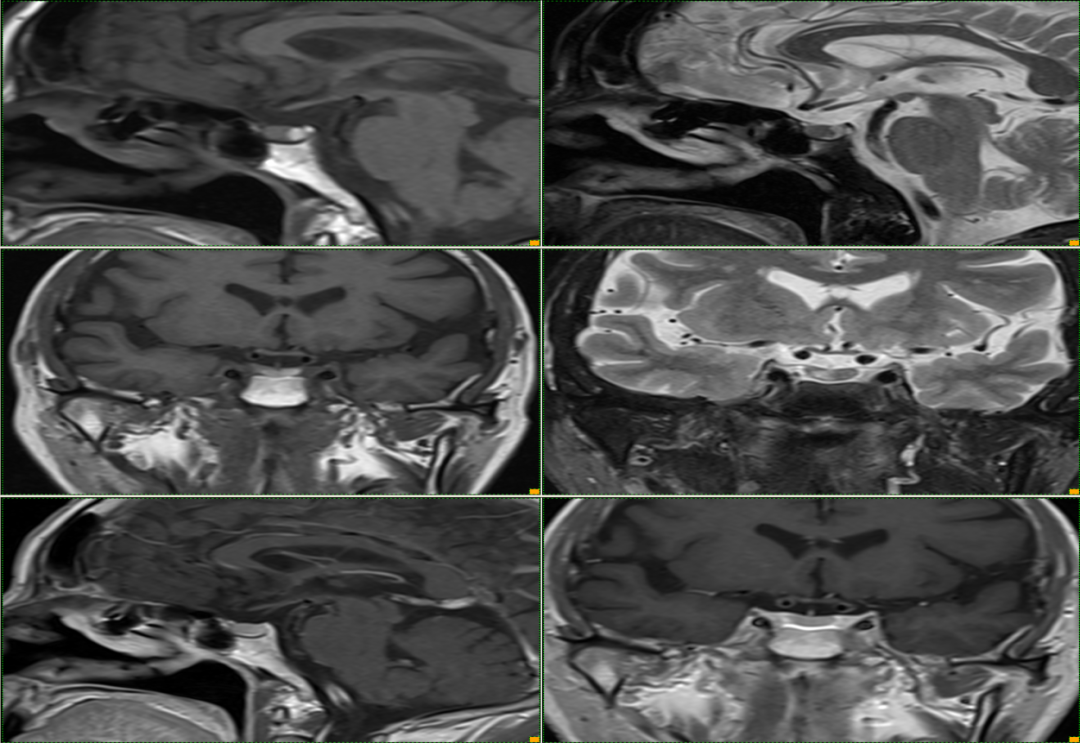

case 1: f/63y 头痛

T1WI 示垂体内高信号病变,增强无强化,左侧鞍旁脑膜瘤

case 2: f/46y24042 头痛

等 T1WI、等 T2WI 伴内低信号结节

case 3: f/34y 头晕 2 天入院,既往植物神经功能紊乱病史 2 年

T1WI 高 T2WI 低信号病变

T1WI 示垂体内高信号病变,增强无强化

case 4: M53Y,急性起病, 间断头痛 3 天

矢状位 T2WI 示:高信号囊肿和其内低信号结节

case 5:m/52y

T1WI 示垂体内高信号病变,位于正常 T1WI 高信号的神经垂体前方

case 6:m/57y 眩晕反复发作

case 7:M/49y 头晕 3D

T1WI 高、T2WI 等信号结节,增强未见强化

case 8:F/56Y 头晕 1y

case 9:女,28y,头晕头痛

case 10:偶然发现,无症状,10 年后再次检查发现病灶消失

case 11:正常垂体位于囊肿下方——「杯中卧蛋」征

case 12:m/46y,无症状,偶发

垂体柄前方及中间部见两个 T1WI 等 T2WI 压脂低信号,增强无强化

case 13:

小条状 T1WI 高 T2WI 压脂略低增强无强化

case 14:女,39 Y

冠状位扁平,呈「蝴蝶结」状改变